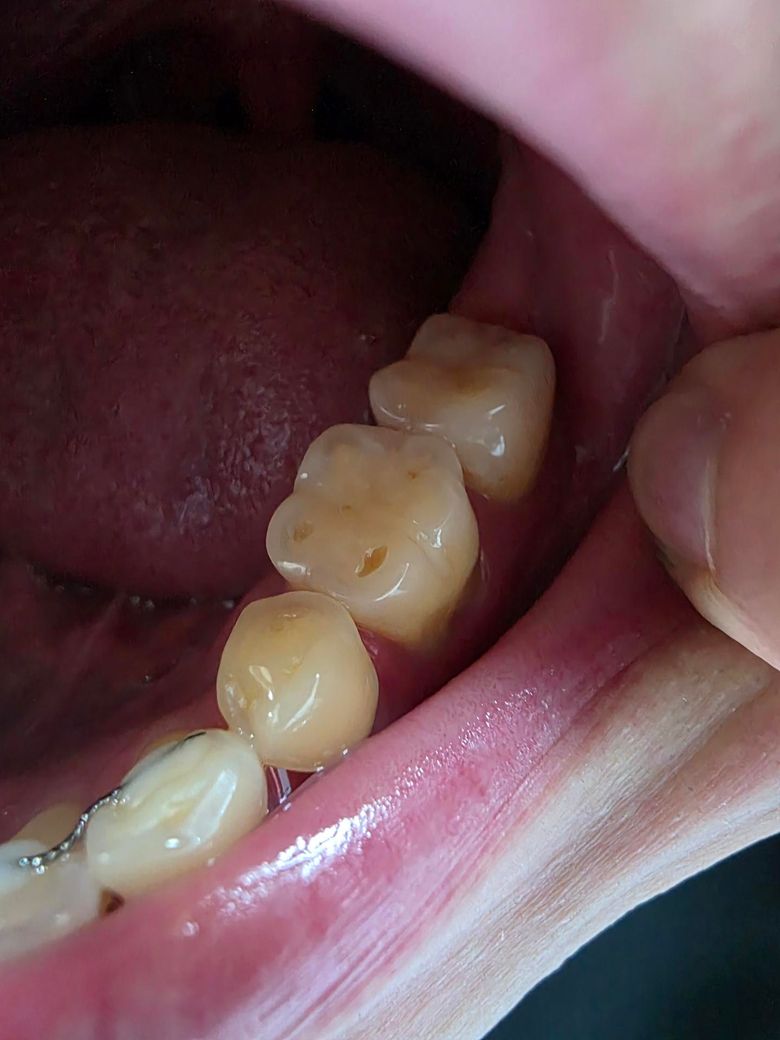

치아 단면에 구멍 난건가요?????

어금니쪽에 구멍이 난것같이 보이는데

충치인가요?? 치료가 필요한건지요??

손톱으로 만져보니 좀 패인것 같고 살짝 시린거같기도한데 통증은 없어요!

반대쪽에는 없는데 이게 뭔가요??

사진으로 봤을 경우 마모증으로 보입니다. 마모증은 치아에 과도한 힘이 가해졌을 경우 치아가 마모가 되면서 생기는 증상으로 치아에 가해지는 힘을 줄여줘야 합니다. 지속적으로 힘이 강하게 가해지게 되면 치아의 마모가 더 진행하게 되어 치아가 시리거나 불편감을 느낄 수 있습니다.

치아에 구멍난건 맞지만 다른 이유가 아니라 치아가 교합되면서 교모되서 그런거니 크게 걱정은 안하셔도 될것같습니다.

전반적으로 주변치아의 교두도 편평하고, 이갈이나 이악물기 습관으로 인해 치아가 많이 마모된 것 같습니다.

말씀하신 부위는 치아 특정부위가 패였네요

시리다면 떼워주면 될 것 같습니다

그보다는 구강 악습관이 있다면 개선하는 것이 좋을 것 같습니다